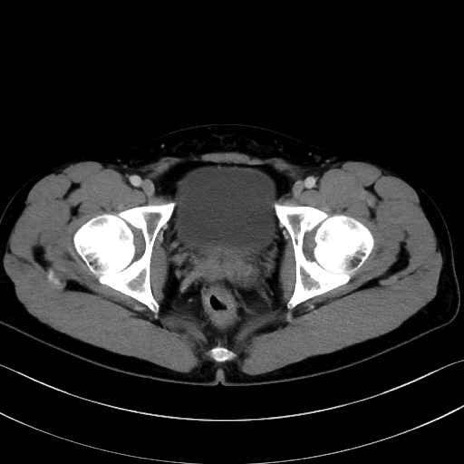

大腿方形筋(Quadratus femoris muscle)のCT画像の解剖

内閉鎖筋 (Obturator internus)

外閉鎖筋 (Obturator externus)

大腿方形筋 (Quadratus femoris)